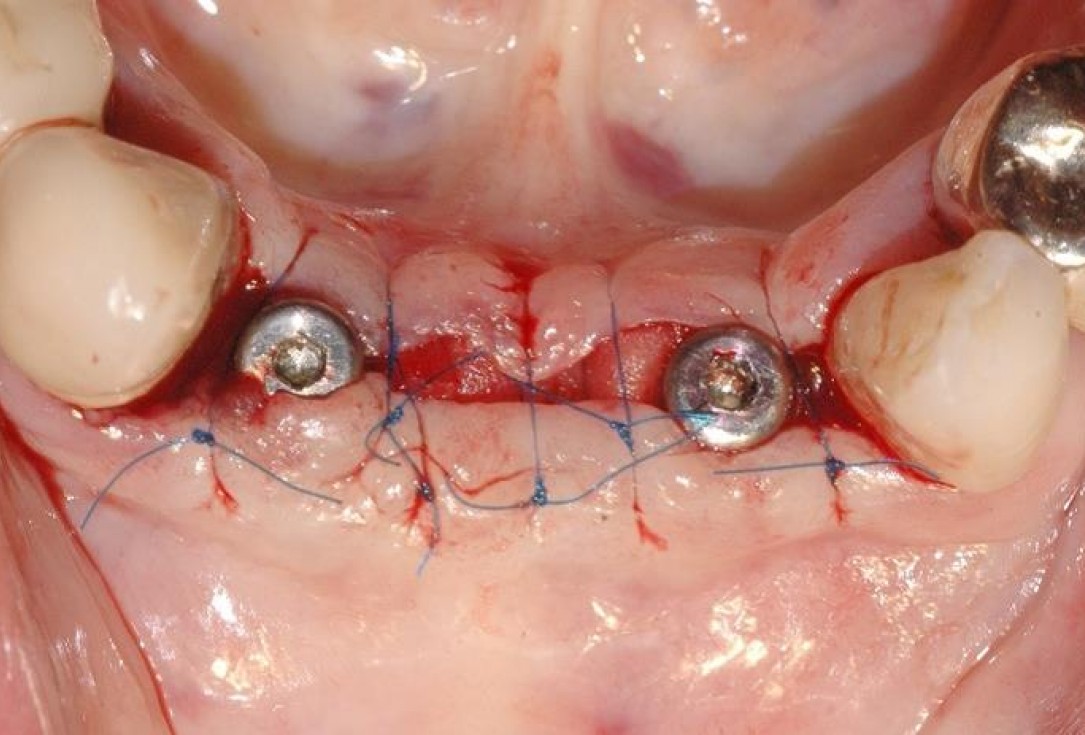

7/15 - Tension-free wound closure with different suturesSoft tissue augmentation and GBR with mucoderm® and maxresorb® - Dr. S. Scherg